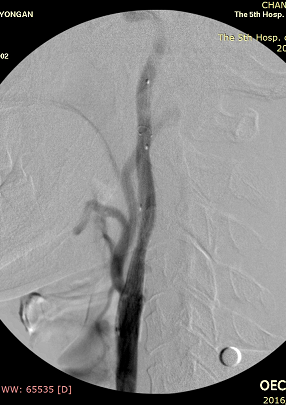

手术如期进行,正如术前所料,右颈动脉斑块的性质不佳,手术难度、风险极大,但王兵副院长带领崔文军副主任医师和安乾、司江涛主治医师克服了重重困难,有惊无险地顺利完成手术,成功地在凹凸不平的血管内、斑块上置入了一枚支架,解除了狭窄、改善了血流、阻隔了斑块,达到了非常满意的效果。术后患者头晕症状很快消失,1周后顺利出院,恢复了正常的生活。

术中支架置入后造影